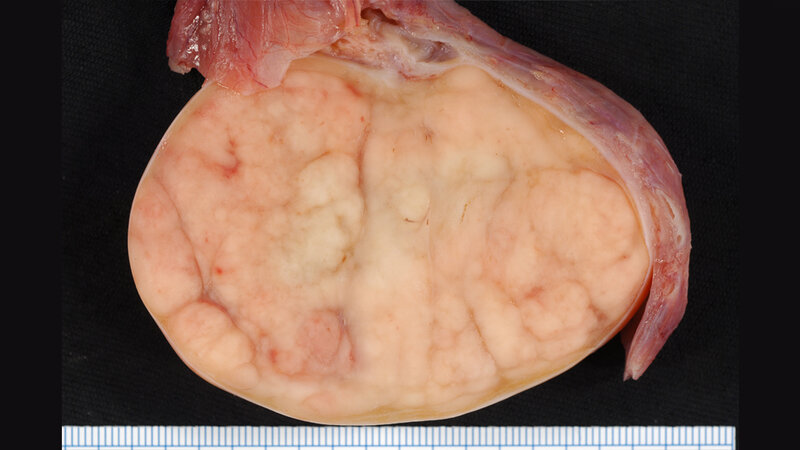

Die häufigste Tumorerkrankung bei Männern zwischen 20 und 40 Jahren ist der Hodenkrebs, weshalb er auch als „der Krebs des jungen Mannes“ bezeichnet wird. Etwa 4.000 Männer erkranken jährlich deutschlandweit, allein in Hamburg sind es etwa 200 Männer pro Jahr. Die Zahl der Erkrankungen steigt seit Jahren an. Der Grund dafür ist nicht bekannt, vermutet werden aber Umwelteinflüsse. Die Entdeckung des Tumormarkers und die Entwicklung eines Bluttests zum Nachweis durch das Forscherteam erleichtern nun nicht nur die sichere Früherkennung von Hodentumoren und damit die Heilungschancen, sondern ebenfalls die Beurteilung des Therapieerfolges und die oft langjährige Nachsorge.

Bereits 2012 konnte das Forschungsteam in der Vorstudie über den neuen Tumormarker bei Hodentumoren berichten. Das Ergebnis mehrjähriger Folgestudien ist nun ein Verfahren zur sicheren Bestimmung der Tumormarker. Der sogenannte Signalstoff M371 wird von den Hodenkrebszellen gebildet und in die Blutbahn ausgeschüttet. Die Urologen um Prof. Dieckmann und seine Partner von der biologischen Fakultät der Universität Bremen konnten zeigen, dass bereits sehr kleine Tumore von weniger als 1 cm Durchmesser den Signalstoff abgeben. „Dies ist ein großer Fortschritt“, so Dieckmann, „denn der M371-Test ist bei mehr als 90 % aller Hodentumoren anwendbar. Die bisherigen Markerstoffe sind nur bei etwa 50 % aller Patienten ausgeprägt. Der neue Test hilft bei der Früherkennung, bei der Ausbreitungsdiagnostik, bei der Feststellung des Therapieerfolges und vor allem bei der Früherkennung von Rückfällen. Wir denken auch, dass bei der Nachsorge viele der schädlichen, belastenden und teuren Röntgenuntersuchungen mit dem Test nicht mehr nötig sind.“